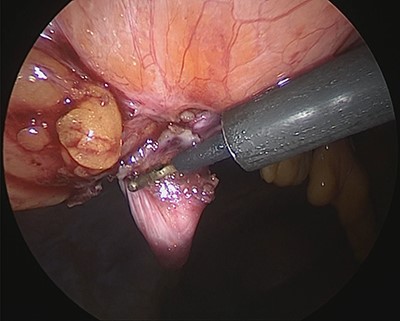

Under general anesthesia, with the patient in the lithotomy position, a 5-mm trocar was inserted into the lower right abdomen using the optical method. Observation of the abdominal cavity revealed a hernia orifice with a diameter of ~1 cm at the upper aspect of the umbilicus (Fig. 3). Two additional 5-mm trocars were inserted into the left side of the abdomen. The hernia sac was significant scarring. We then made an incision around the hernia orifice using a hook-type electrocautery electrode to expose the muscle layer (Fig. 4). The hernia sac was pushed from the surface of the body using a pean, inverted into the abdominal cavity, and excised as much as possible using electrocautery (Fig. 5). At that point, we employed the VersaOne™ Fascial Closure System to close the fascia and peritoneum at the port site.